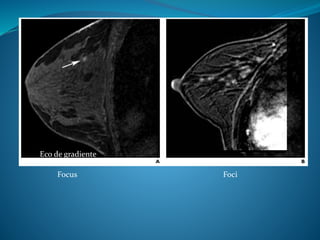

1) Focus o foci

1) Focus o foci: Son realces pequeños < 5 mm que

no pueden ser especificados. Estos son

estables en las imágenes de seguimiento y

pueden deberse a cambios hormonales.

Focus Foci

Eco de gradiente

BI-RADS Incluye: * Localización dela lesión. * Evaluación morfológica del realce. 1) Focus o foci 2) Masas 3) Realce en no masa 1) Focus o foci: Son realces pequeños < 5 mm que no pueden ser especificados. Estos son estables en las imágenes de seguimiento y pueden deberse a cambios hormonales.